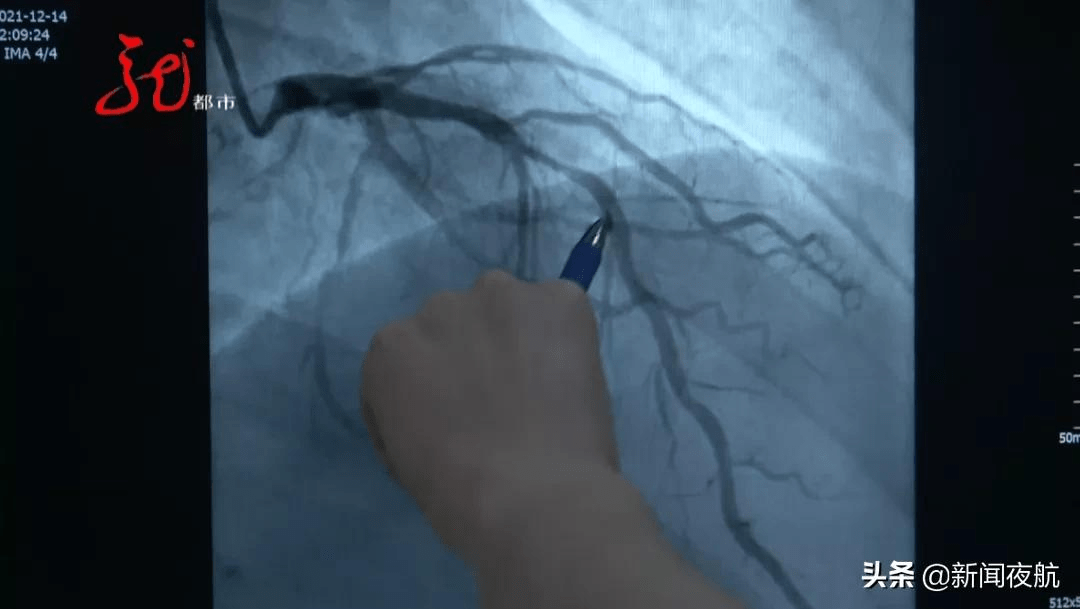

这是患者的右冠状动脉 , 正常的血管我们可以看到 , 从这儿开始 , 这样像一个C字型连接下来 , 而这个患者的血管 , 我们可以看到这个位置之后 , 中间黑颜色的血管消失了 , 完全“断开”了 , 这根血管完完全全地堵死了 。

右冠状动脉 , 是人体心脏的三根大血管之一 。 如果说 , 这是一位70岁老人的心脏 , 出现这种情况还算正常现象 , 而这恰恰是一位36岁男性的心脏 。